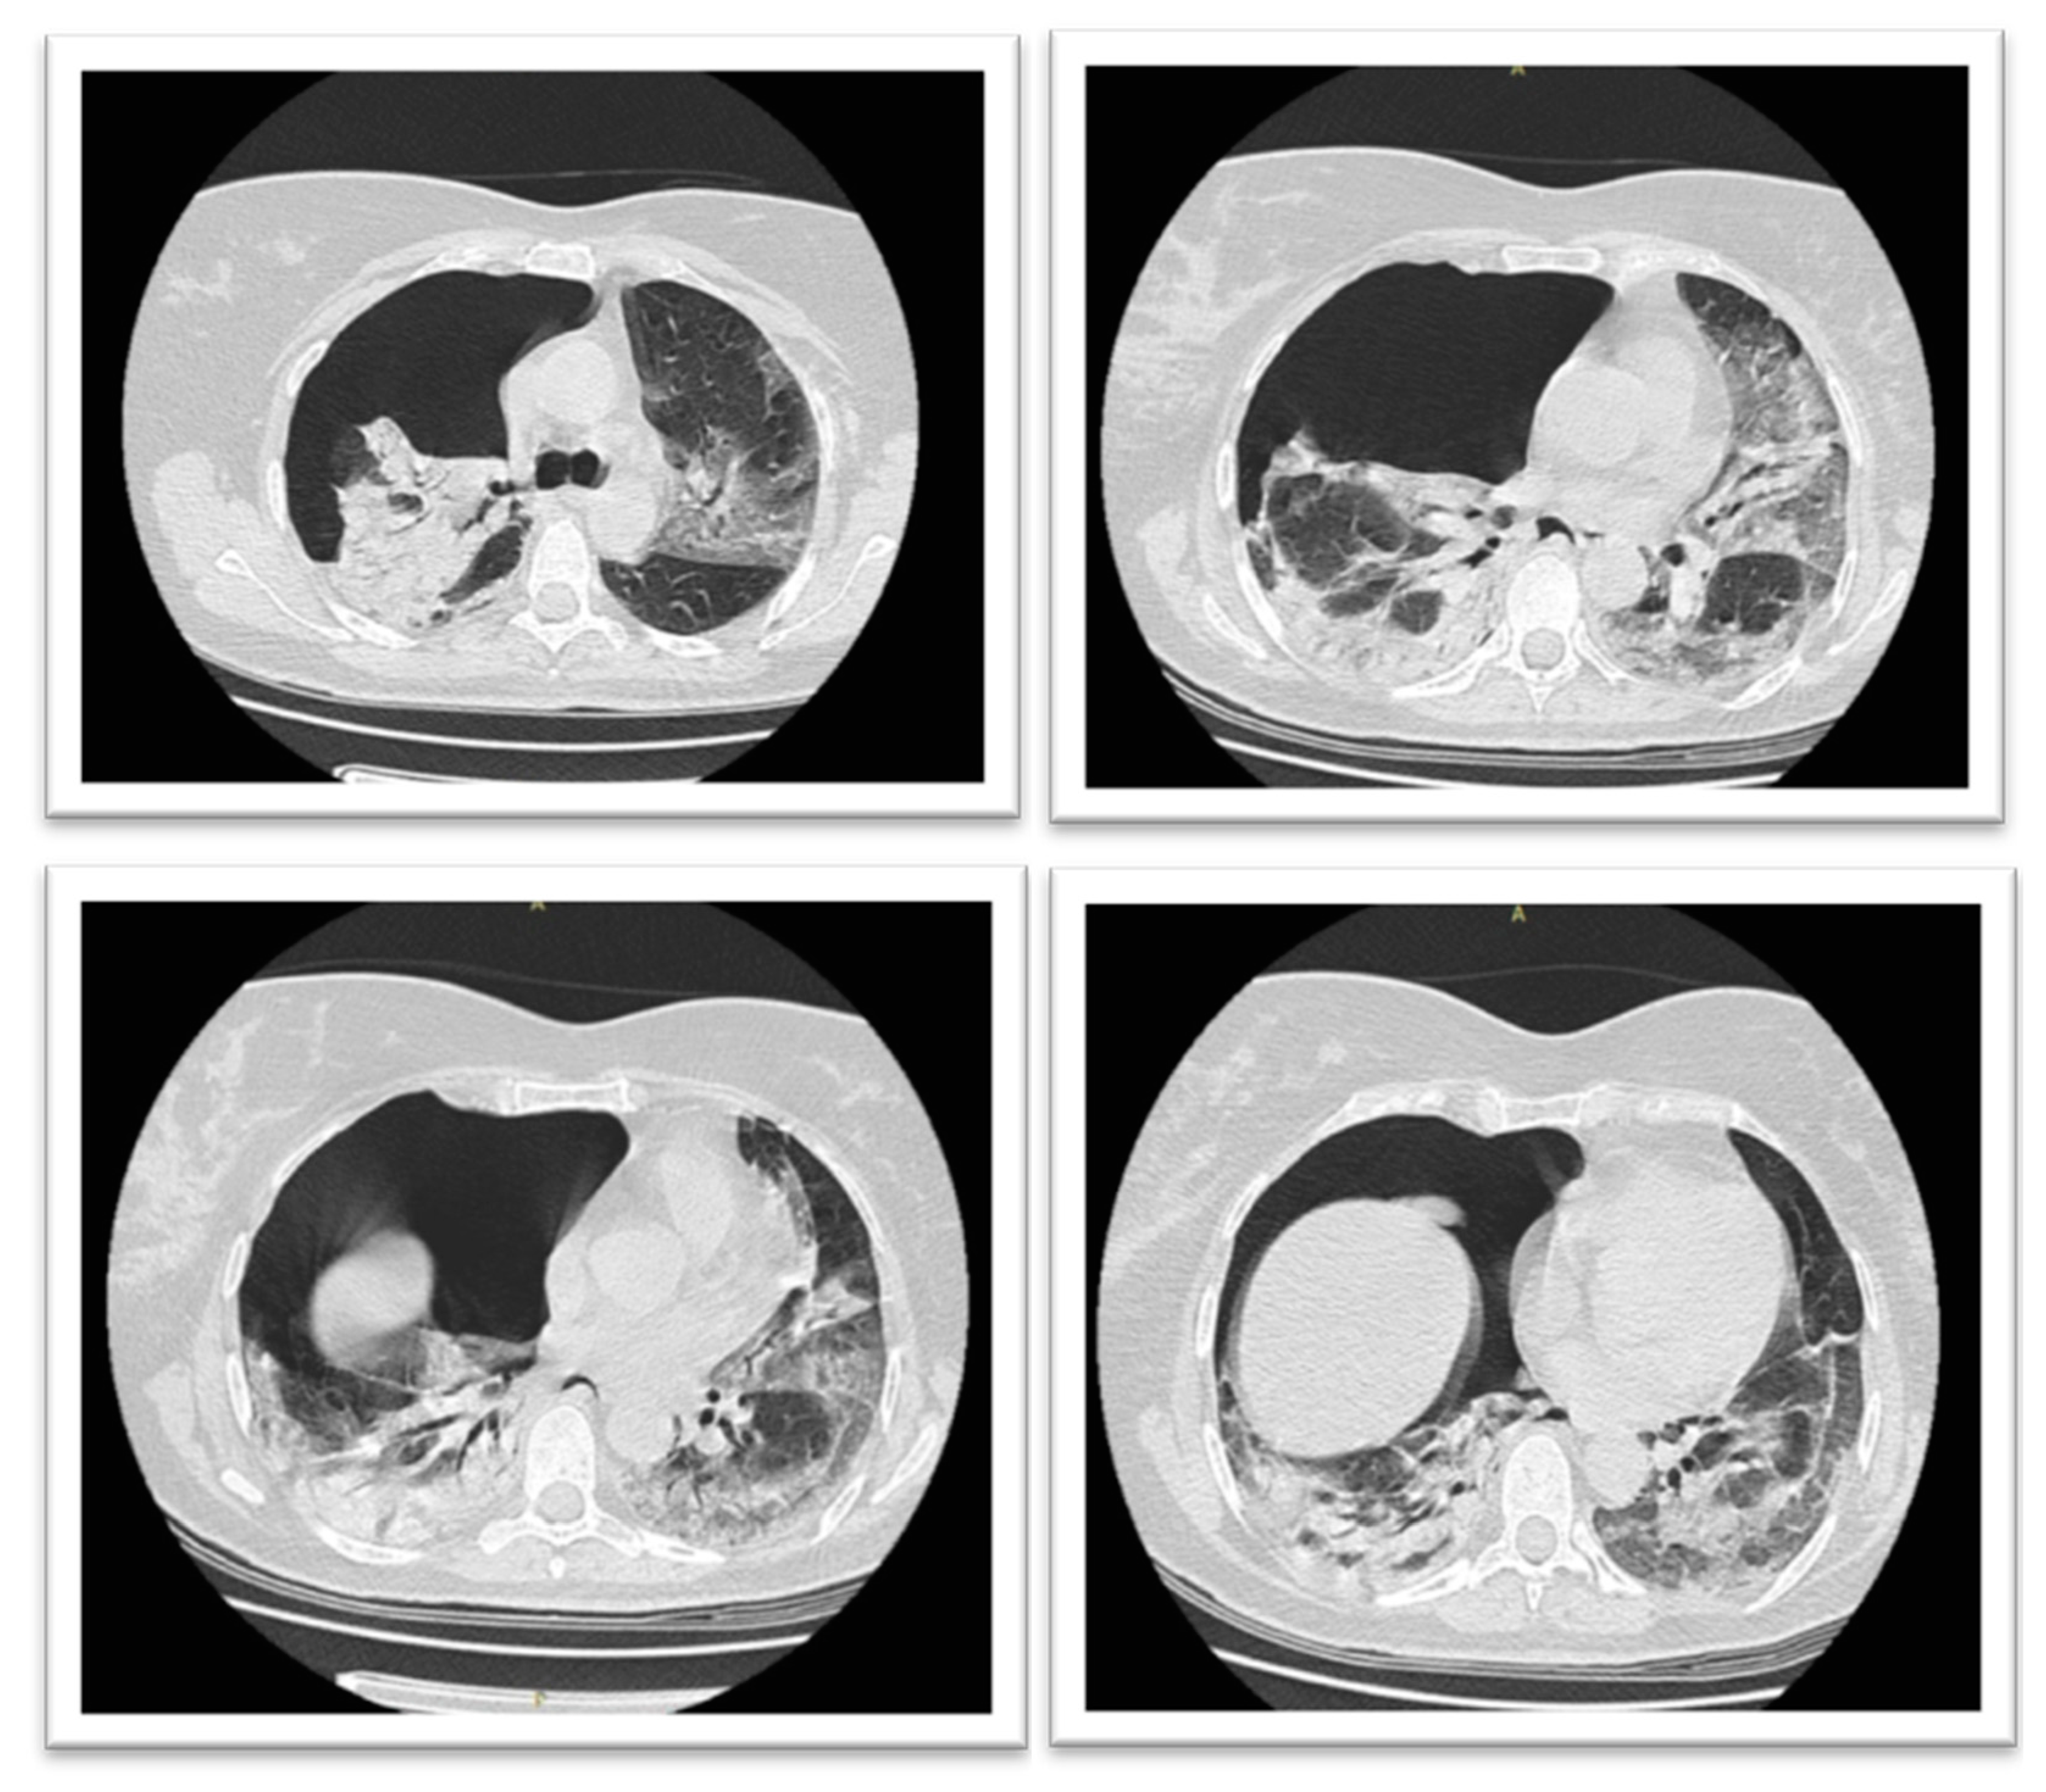

Case Report: Massive Spontaneous Pneumothorax—A Rare Form of Presentation for Severe COVID-19 Pneumonia

2. Case Presentation